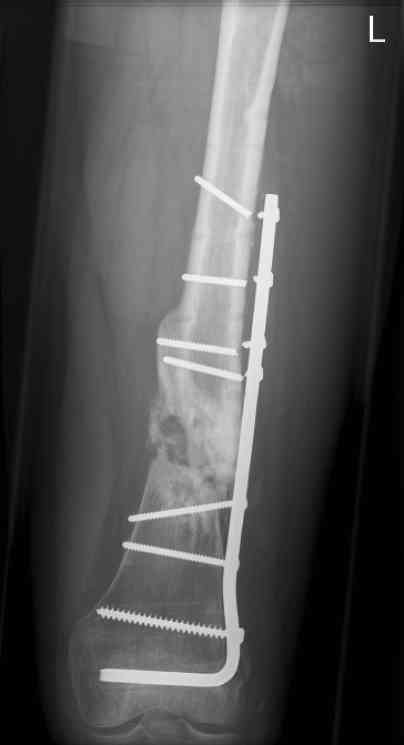

feb 07: retrograde nail + bone graft + BMP

may 07: dynamisation nail

sept 07: locking screw removal (max. dynamisation reached)

nov 07: persistant non-union distal femur; other fractures healed uneventfully.

All with gradual/partial weightbearing etc. Currently 50-100% weight bearing, no pain.

Soft tissues are intact. No smoking or diabetes.CRP <2